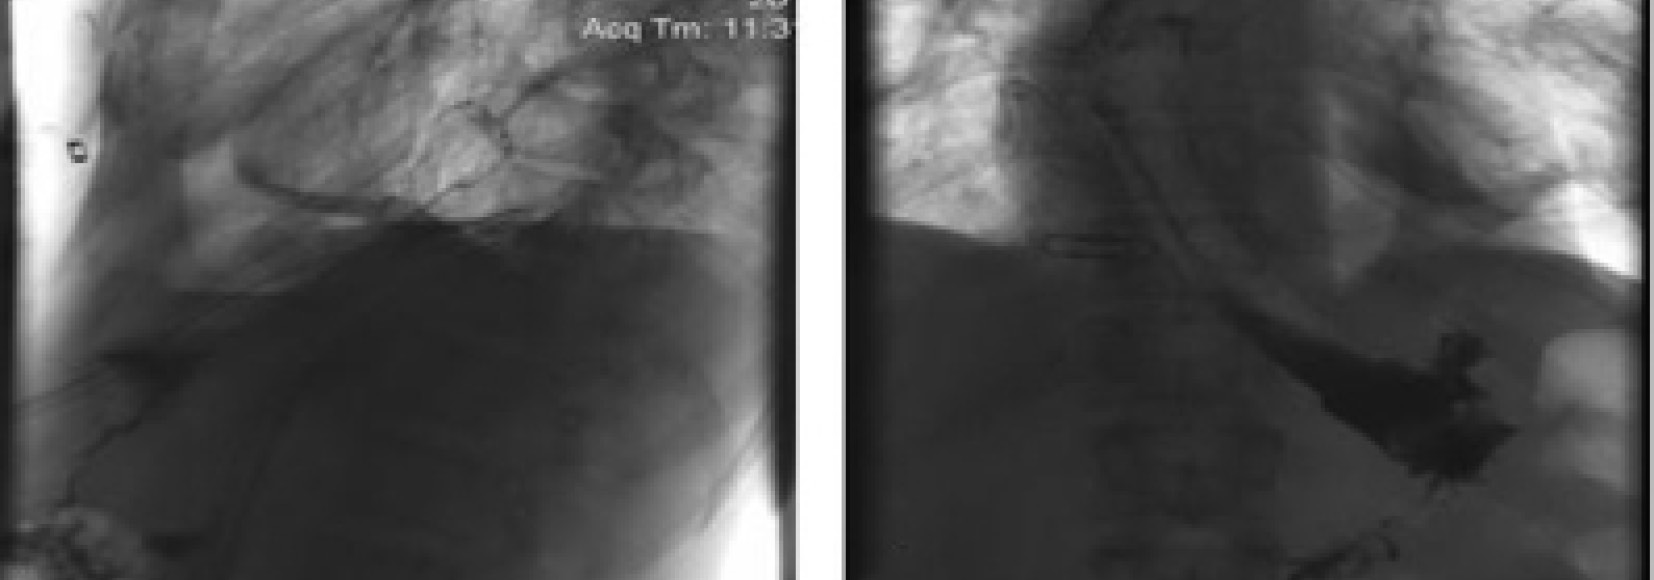

При спиральной компьютерной томографии груди диагностирован затек контраста в обе плевральные полости, признаки медиастинита (рис. 2).

Рис. 2. Компьютерные томограммы (А и Б) в аксиальной проекции. Двусторонний гидроторакс, слева гидропневмоторакс на фоне энтерального зонда и дренированных плевральных полостей

Рис. 3. Рентгенограммы: А — при постановке стента; Б — через 2 дня после установки. Пищевод герметичен, миграции стента и затека контрастного вещества не определяются